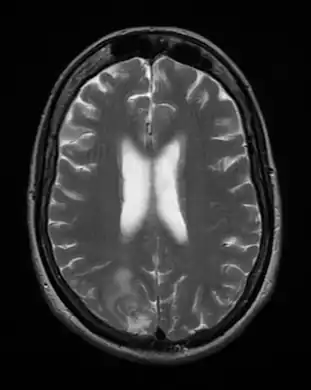

Acute

Acute toxoplasmosis is often asymptomatic in healthy adults.[13][14] However, symptoms may manifest and are often influenza-like: swollen lymph nodes, headaches, fever, and fatigue,[15] or muscle aches and pains that last for a month or more. It is rare for a human with a fully functioning immune system to develop severe symptoms following infection. People with weakened immune systems are likely to experience headache, confusion, poor coordination, seizures, lung problems that may resemble tuberculosis or Pneumocystis jiroveci pneumonia (a common opportunistic infection that occurs in people with AIDS), or blurred vision caused by severe inflammation of the retina (ocular toxoplasmosis).[15] Young children and immunocompromised people, such as those with HIV/AIDS, those taking certain types of chemotherapy, or those who have recently received an organ transplant, may develop severe toxoplasmosis. This can cause damage to the brain (encephalitis) or the eyes (necrotizing retinochoroiditis).[16] Infants infected via placental transmission may be born with either of these problems, or with nasal malformations, although these complications are rare in newborns. The toxoplasmic trophozoites causing acute toxoplasmosis are referred to as tachyzoites, and are typically found in bodily fluids.[17][18]

Due to the absence of obvious symptoms,[13][14] hosts easily become infected with T. gondii and develop toxoplasmosis without knowing it. Although mild, flu-like symptoms occasionally occur during the first few weeks following exposure, infection with T. gondii produces no readily observable symptoms in healthy human adults.[7][21] In most immunocompetent people, the infection enters a latent phase, during which only bradyzoites (in tissue cysts) are present;[22] these tissue cysts and even lesions can occur in the retinas, alveolar lining of the lungs (where an acute infection may mimic a Pneumocystis jirovecii infection), heart, skeletal muscle, and the central nervous system (CNS), including the brain.[23] Cysts form in the CNS (brain tissue) upon infection with T. gondii and persist for the lifetime of the host.[24] Most infants who are infected while in the womb have no symptoms at birth, but may develop symptoms later in life.[25]

The classic triad of congenital toxoplasmosis includes: chorioretinitis, hydrocephalus, and intracranial arteriosclerosis.[65] Other consequences include sensorineural deafness, seizures, and intellectual disability.[66]Congenital toxoplasmosis may also impact a child's hearing. Up to 30% of newborns have some degree of sensorineural hearing loss.[67] The child's communication skills may also be affected. A study published in 2010 looked at 106 patients, all of whom received toxoplasmosis treatment prior to 2.5 months. Of this group, 26.4% presented with language disorders.[68]